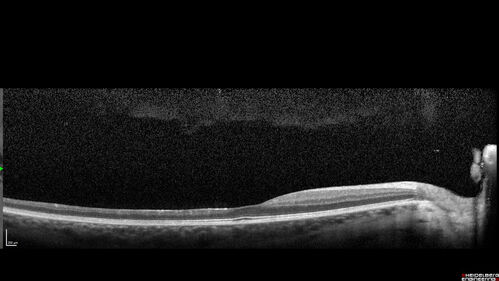

Coats Plus Syndrome - Cerebroretinal microangiopathy with calcifications and cysts (CRMCC)

38 year old female CTC1 positive with Coats Plus Syndrome. This case was published https://pmc.ncbi.nlm.nih.gov/articles/PMC10649444/